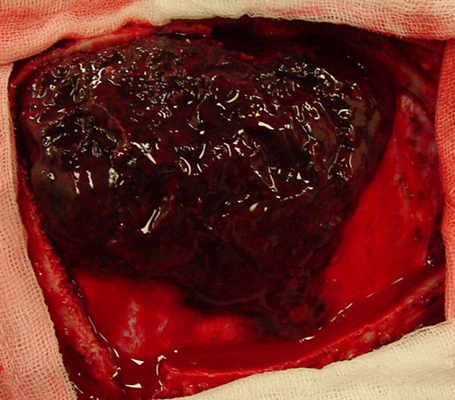

顱內血腫圖片

硬膜下血腫 (45)

硬膜下血腫 (46)

硬膜下血腫 (47)